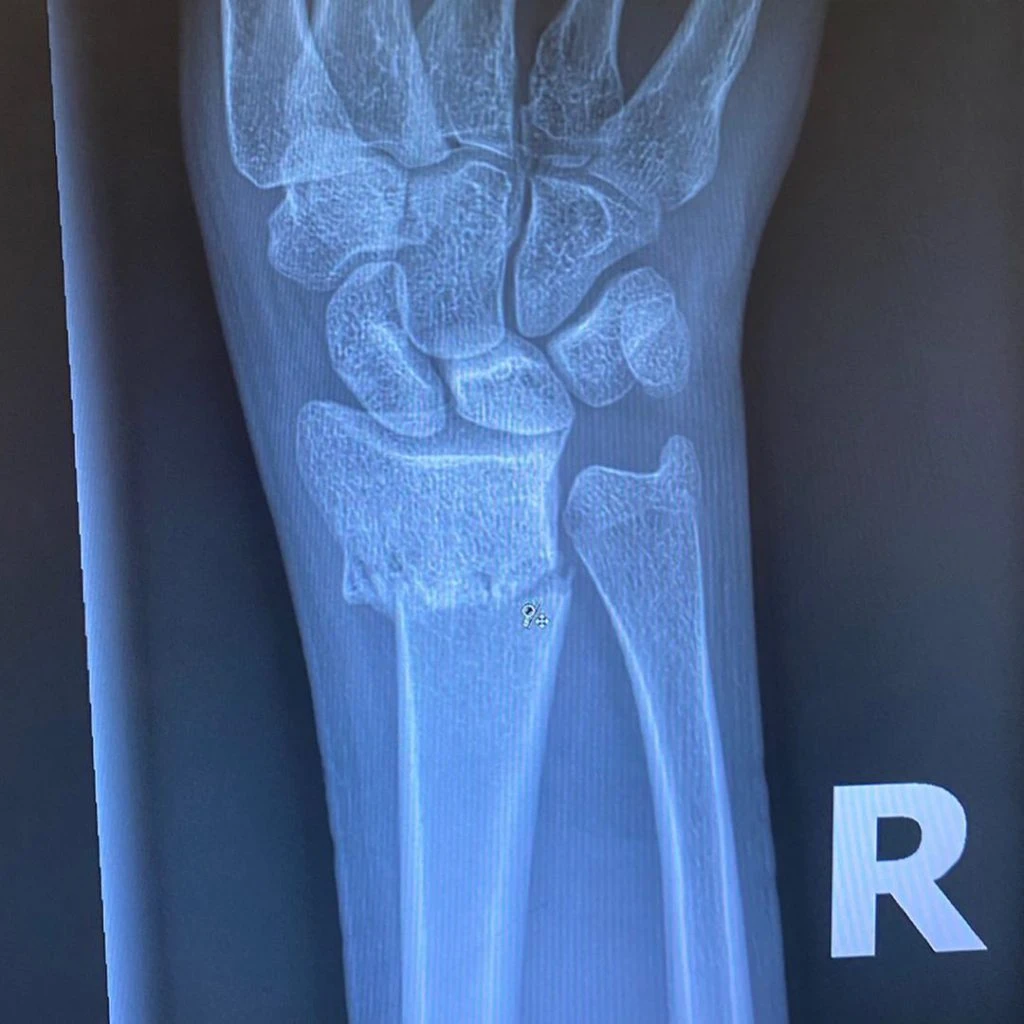

Kaia Gerber anunció en sus redes que había tenido un accidente, sin especificar cuál fue, hasta que sus millones de seguidores se enteraron lo que le había pasado: se quebró su muñeca izquierda.

Ya con la noticia circulando y para compartir y tranquilizar a sus más de cinco millones y medio de seguidores, subió una foto mostrando su lesión. "Está todo bien", aseguró una de las modelos más cotizadas del mundo.